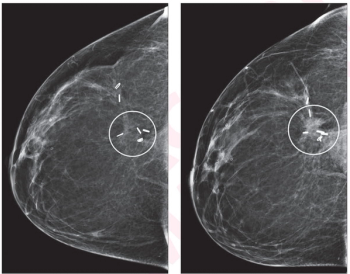

For women who have had radial scars detected on digital breast tomosynthesis (DBT) exams, researchers noted a 5 percent upstaging rate to cancer, according to a recent study.

In a study of over 30,000 screening digital breast tomosynthesis (DBT) exams for over 8,000 women, researchers found a specificity rate of 95.1 percent, a false negative rate of 2.1 (per 1,000 exams) and an abnormal interpretation rate (AIR) of 5.7 percent.